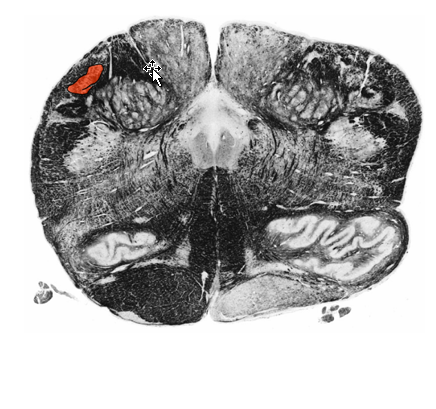

Describe the Rostral Medulla

@ level?

Appearance of?

What enlarges?

Describe Inferior salivatory nucleus (of IX)

Origin of?

Receives influences from

Structures and relationship to restiform body

between restiform body and Inferior olive.

Now Part of Restiform Body:

Reticular Formation Function

@ Level of CN IX & VIII

Appearance

dorsal and ventral cochlear nuclei (C.N. VIII)

Inferior salivatory nucleus (of IX)

Nucleus prepositus:

(i.e. c. participates in visual fixation on objects)

Enlarges:

Restiform body

Reticular formation

Origin of:

Parasymp motor fibers to parotid gland.

Synapse @ Otic

Postgang supply parotid gland

hypothalamus and olfactory system.

Structure between restiform body and Inferior olive.

Spinal trigeminal nucleus (and tract),

anterolateral system,

rubrospinal tract

anterior spinocerebellar tract

Posterior spinocerebellar tract and cuneocerebellar tract

Reticular Formation:

Function:

Wide range including consciousness and sleep.